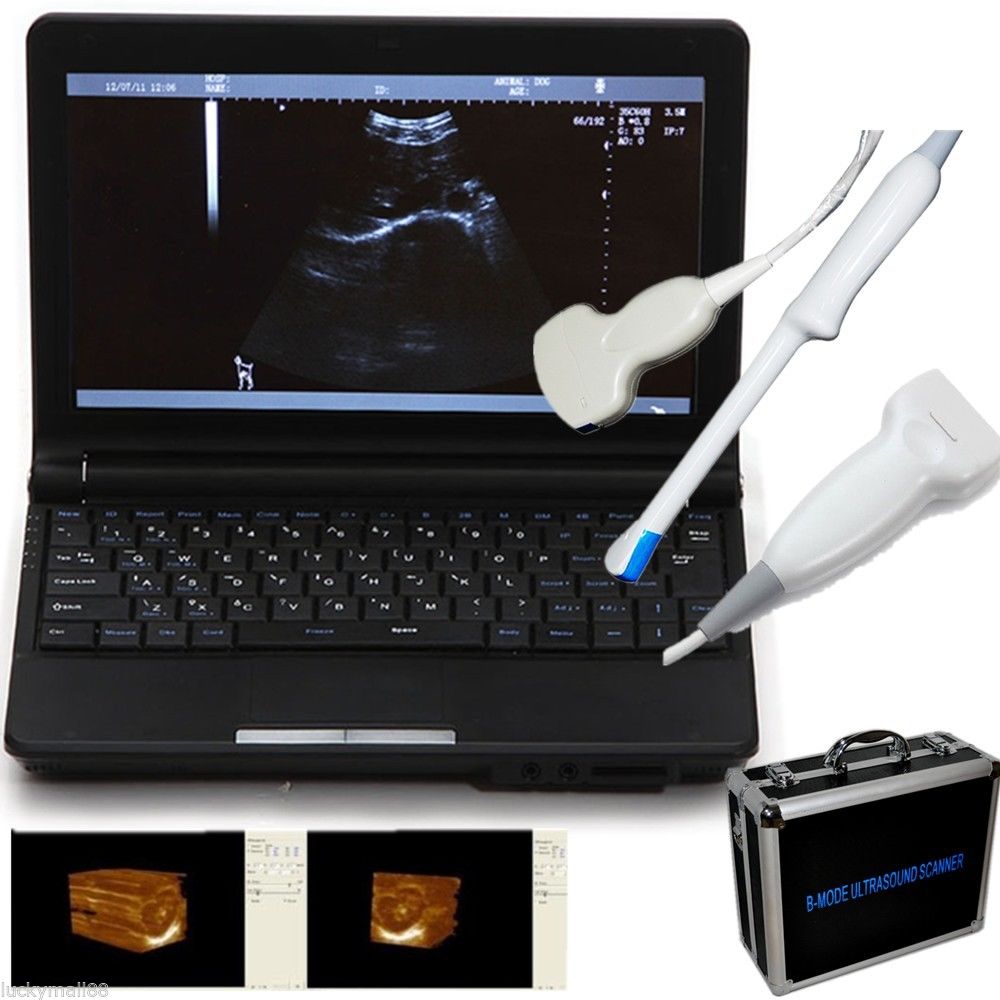

DIAGNOSTIC ULTRASOUND MACHINES FOR SALE

Ultrasound Scanner machine Rectal Probe 3D Laptop Machine Digital Veterinary AA 190891879431

Sale price$ 1,866.31

Regular price$ 2,275.99

Ultrasound Scanner Veterinary Pregnancy US-96 with 3.5 MHz Convex Probe.

Sale price$ 1,758.07

Regular price$ 2,143.99

DIAGNOSTIC ULTRASOUND MACHINES FOR SALE

Ultrasound Scanner Veterinary Pregnancy US-96 with 7.5 MHz Rectal Probe.

Sale price$ 1,844.18

Regular price$ 2,249.00